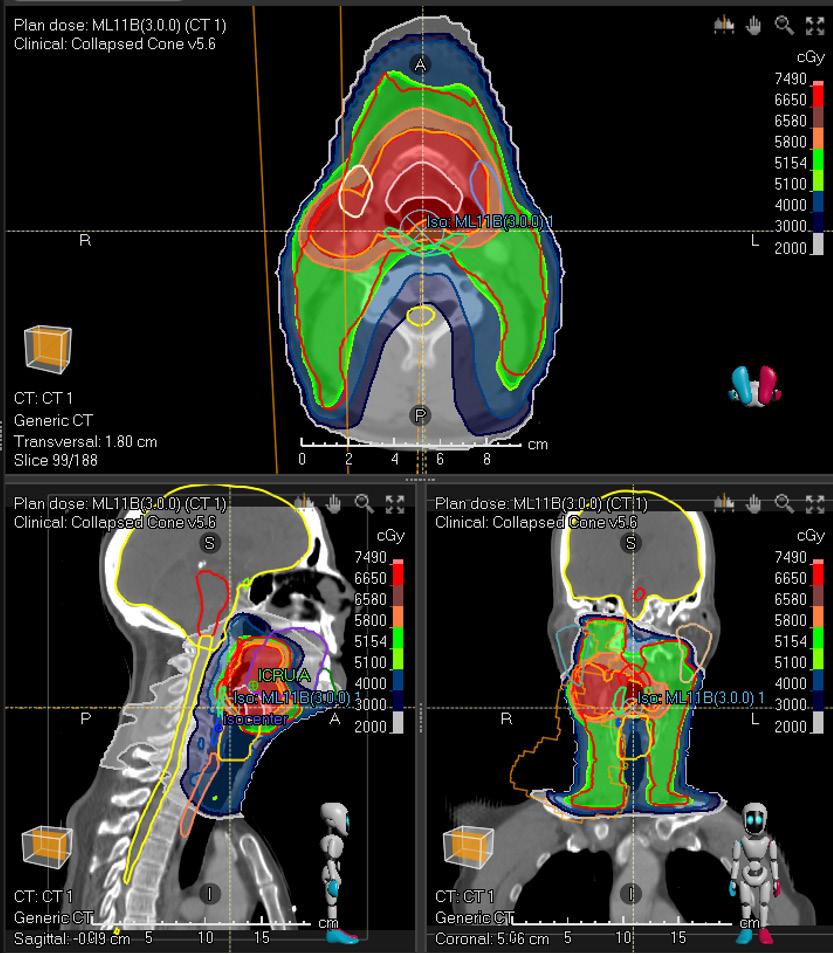

MODEL OVERVIEW

Treatment site Head and neck

Modality Photons

Treatment technique Validated for VMAT

Primary prescription [cGy] 7000

Number of fractions 35

Dose per fraction [cGy] 200

MODEL PROTOCOL

ROI Clinical goals

PTV High At least 6650 cGy dose at 98.0 % volume

PTV High At most 7490 cGy dose at 1.8 cm³ volume

PTV Low At least 5320 cGy dose at 98.0 % volume

Spinal Cord At most 4500 cGy dose at 0.0 % volume

Brain At most 5800 cGy dose at 1.0 cm³ volume

Brain At most 6800 cGy dose at 0.0 % volume

Cochlea L/R At most 4500 cGy dose at 50.0 % volume

Cochlea L/R At most 5500 cGy dose at 5.0 % volume

Parotid L/R At most 2600 cGy dose at 50.0 % volume

Constrictor Muscle I/M/S At most 5500 cGy dose at 50.0 % volume

Brainstem At most 5400 cGy dose at 0.0 % volume

Submandibular Gland L/R At most 3500 cGy dose at 50.0 % volume

Cavity Oral At most 3000 cGy dose at 50.0 % volume

Esophagus S At most 3000 cGy dose at 50.0 % volume

Optic Nerv L/R At most 5400 cGy dose at 0.0 % volume

Eye L/R At most 3000 cGy dose at 0.0 % volume

Lacrimal Gland L/R At most 2500 cGy dose at 50.0 % volume

Glottis At most 4000 cGy dose at 50.0 % volume

Larynx SG At most 4000 cGy dose at 50.0 % volume

Bone Mandible At most 7200 cGy dose at 0.0 % volume

Validation patient example